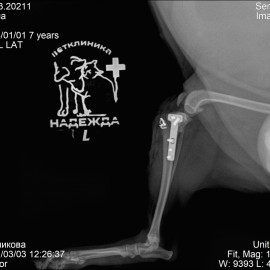

Наш пациент возрастом 7 лет по кличке Кнопа.Обратились в клинику " Надежда" с жалобами на хромоту на заднюю левую лапу после прыжка с дивана.Проведен осмотр и рентгенологические исследования, поставлен диагноз: разрыв передней крестообразной связки, пателлярный вывих. Была проведена сочетанная операция: TPLO левой большеберцовой кости, транспозиция шероховатости левой большеберцовой кости.

Снимок 2 после операции